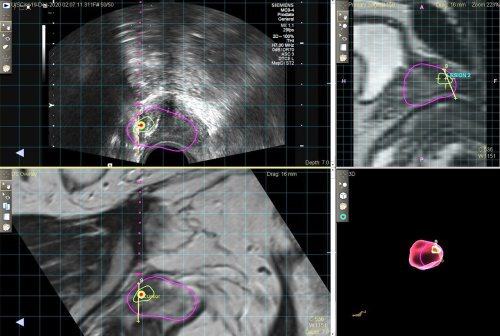

Op. Dr. Emir Akıncıoğlu, sözlerine şöyle devam etti: “MR Füzyon Biyopsi cihazıyla klasik biyopside atlanabilecek olan kanser odakları başarılı şekilde tespit ediliyor ve tam olarak belirlenen hedef noktalardan örnekler alınabiliyor. Bunun için önce MR filmi çekiliyor, sonrasında kanser şüpheli yerler belirlenerek füzyon biyopsi cihazına görüntüler yükleniyor. Ardından işlem esnasında gerçek zamanlı olarak ultrason ve MR görüntüleri örtüştürülüyor. İşlem sırasında şüpheli yerlerden tam isabet ile örnekleme yapılabiliyor. Hastalıklı prostatlı dokularının gözden kaçırılması riskini neredeyse sıfıra indiriyoruz. Bunun için teknoloji ve tecrübe gerekiyor. Biz de ekip olarak son bir yıl içerisinde 100'den fazla hastaya başarıyla bu işlemi uyguladık. En yüksek standartlarda hastalarımıza hizmet vermeye de devam ediyoruz”